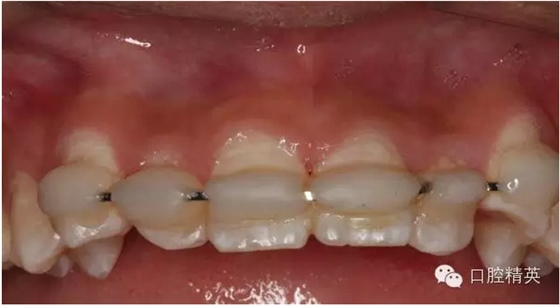

圖2.口內(nèi)整體影像

圖6.固定一個(gè)月后的唇側(cè)影像,牙齦及粘膜正常?;颊邿o(wú)任何自覺(jué)癥狀。